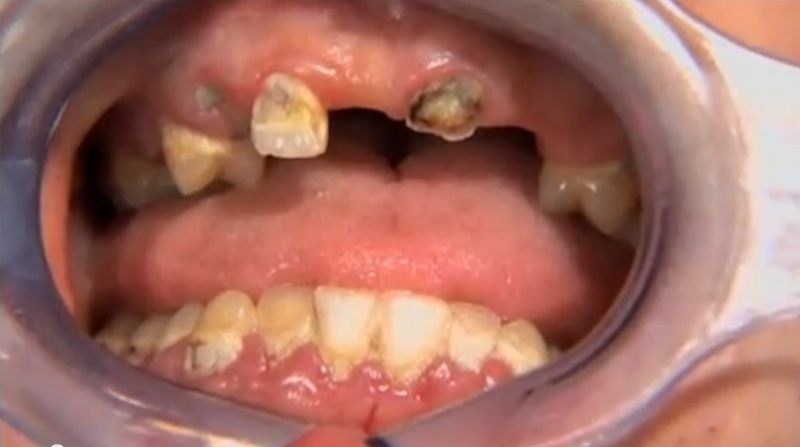

You and your patients will benefit from this practical video! Almost every dentist does some oral surgery, but very few have had significant education in surgical procedures. Karl and Gordon have made a practical, easily understood, step-by-step live video showing necessary concepts, techniques, and instruments needed for oral surgery in your practice. Frequently needed techniques are emphasized, including use of luxators, inter-radicular bone removal, mesial and distal troughing, sectioning roots, and buccal bone removal. Receive many tips on how to make routine surgery faster, easier, and more enjoyable.

- Patient Surgery